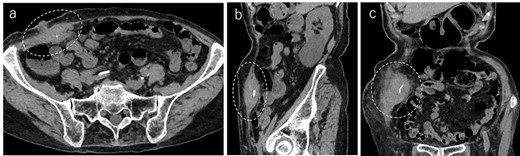

A 90-year-old woman was referred to our hospital complaining of a painful mass located in the right lower quadrant of her abdomen. She had a history of acute appendicitis, for which she underwent an appendectomy approximately 70 years prior to the current consultation. She first noticed the pain 6 months prior to consultation. In the interim, the pain gradually worsened. Upon physical examination, a palpable tumor was present below the appendectomy scar. Yellowish pus was removed from the skin over the tumor (Fig. 1). Computed tomography (CT) revealed a tumor in the abdominal wall under the surgical scar of the appendectomy (Fig. 2a). The tumor was 60 mm in width and contained a linear-shaped agent, which was thought to be a foreign body, such as a surgical needle (Fig. 2b and c). Magnetic resonance imaging (MRI) also revealed a low-signal nodule on a T1-weighted image (Fig. 3). Laboratory test results revealed no signs of inflammation. Pus culture revealed no pathogens.

Abdominal CT demonstrated a tumor in the abdominal wall, which extended to the surface of the body (a, encircled); the tumor was 60 mm in width and contained a linear shaped agent; sagittal (b, encircled) and coronal (c, encircled) views.